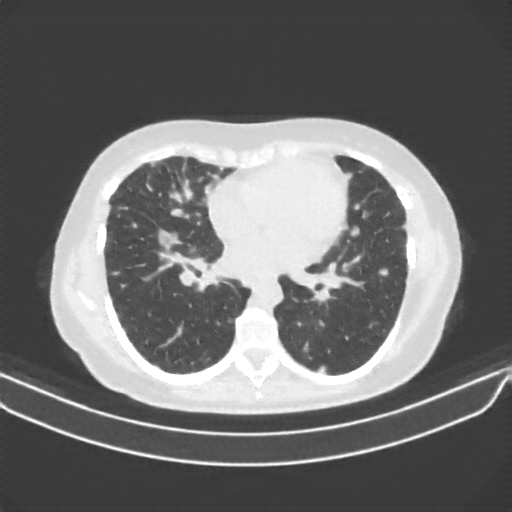

Generated VENOUS CT scan (A→B translation)

Full window (WL 1023.5, WW 4095 β†’ Low βˆ’1024, High +3071)

Lung window (WL -600, WW 1500 β†’ Low βˆ’1350, High +150)

Mediastinum window (WL 40, WW 400 β†’ Low βˆ’160, High +240)